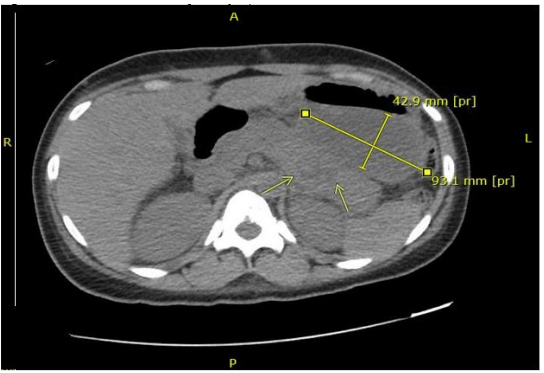

Figure 1: Non-Contrast CT after Hospital Day 15

Newly identified 4.6 x 9.4 x 9.1 cm fluid within the lesser sac not present at time of admission. Additionally, a heterogeneously dense area was identified within the pancreas that was concerning for necrosis although indeterminant without contrast.